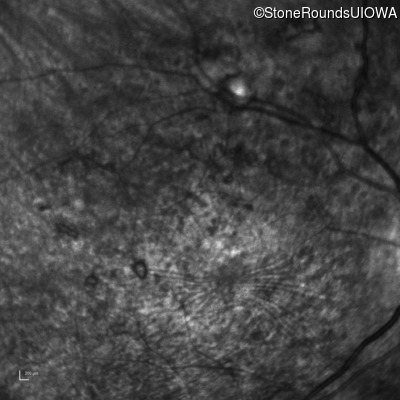

Infrared Fundus Photograph - Left - 20/250 sc

Exemplar